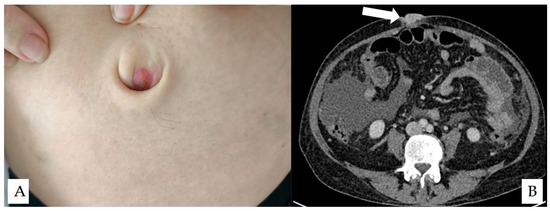

It is with great pleasure that I invite you to submit articles for the “Interesting images” Special Collection. Since we introduced Interesting Images as an article type in Diagnostics, it has served as a valuable resource for the imaging community. Many have relayed that they use these image-based case reports when encountering challenging cases or images of diseases rarely seen. Further, pitfalls are covered by this type of article and may be helpful both for experienced and less experienced image readers in making a correct evaluation.

The interesting Images together serve as a live imaging atlas covering PET, CT, MRI, and other imaging modalities. Therefore, the more cases we publish, the more likely it is that image interpreters with a difficult case can be supported by previously published cases. Although focus until now has largely been on clinical cases, it should be noted that nonclinical cases are also welcome, e.g., from preclinical in vivo imaging, including optical imaging as well as histology images from pathology.